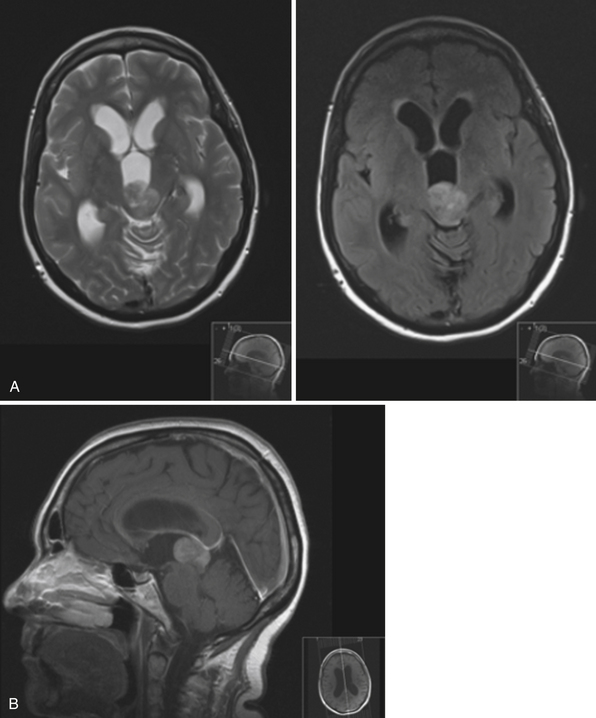

Case 5. Woman, aged 62 years. First normal pressure hydrocephalus …

Hydrocephalus in Children and Adults | Neupsy Key

File:Congenital hydrocephalus MRI02.jpg – Embryology

Hydrocephalus MRI – wikidoc